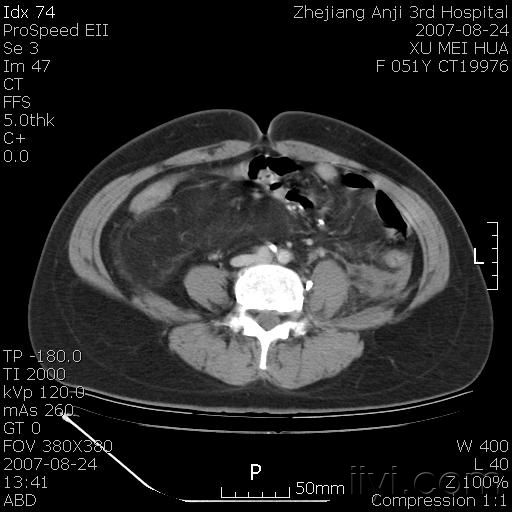

以下是引用还珠格格在2007-8-27 10:19:00的发言:[br]双侧肾脏形态失常,可见巨大的以低密度脂肪为主的混合性肿块,占据中下腹,残留的肾组织轻度强化,增强后肿块内实质部分呈峰窝状强化,低密度区无强化。另左侧肾盂轻度积水。根据病史 考虑 双肾血管平滑肌脂肪瘤可能性大。[br] 鉴别诊断 1、脂肪瘤,境界清楚,肿块内完全是脂肪,几乎没有软组织成分; 2、畸胎瘤:罕见,除有软组织成分外,另一特征是有钙化或骨化影组织。